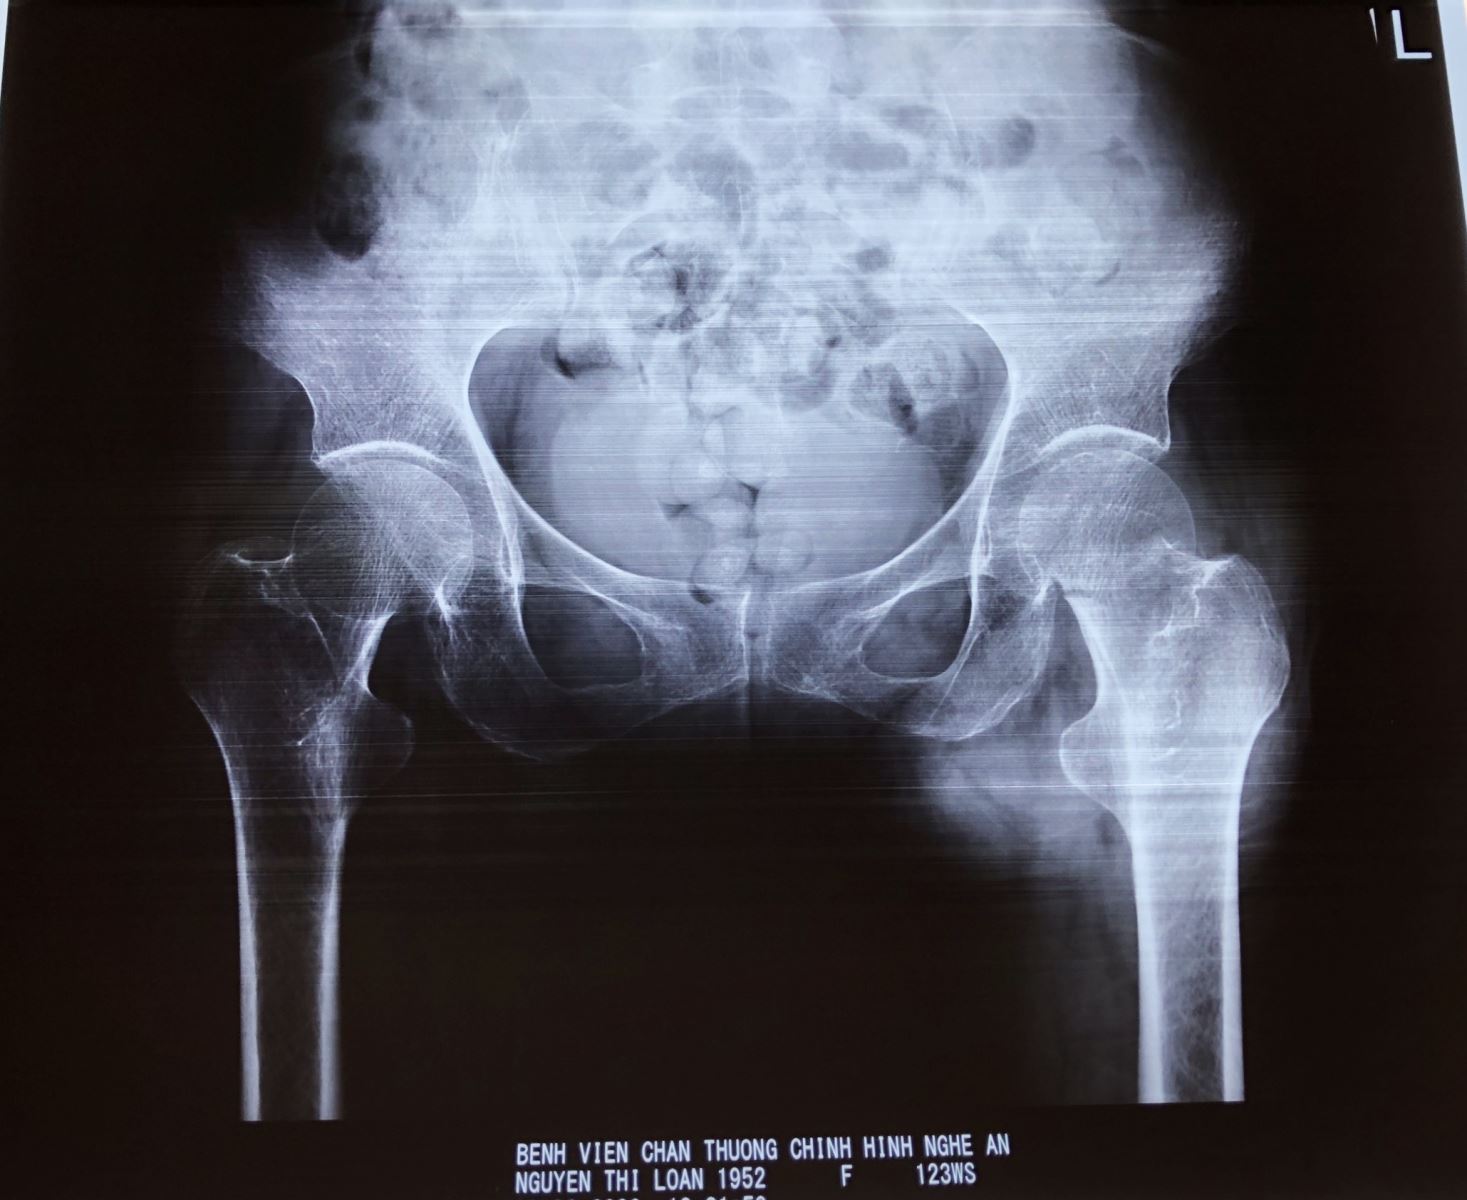

- Chẩn đoán xác định bằng chụp phim xquang khung chậu và khớp háng bên nghi ngờ gãy cổ xương đùi.